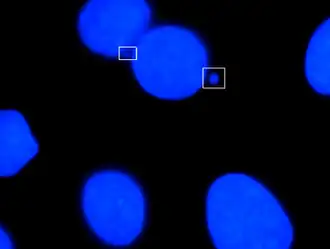

Micronuclei are characterized in the cells that have some sort of DNA damage. This includes damage caused by radiation, harmful chemicals, and random mutations that occur throughout the genome. Micronuclei are small bodies that can be seen budding off of a newly divided daughter cell. Micronuclei can contain a whole chromosome or part of a chromatid. The increased formation of micronuclei is usually an indication of increased DNA damage or mutation. It is characteristically found in cancer cells, or cells that have been exposed to increased risk factors.

Micronuclei are often overlooked in cancer diagnosis and treatment. If observed, they are viewable under a microscope and often located next to other larger nuclei.